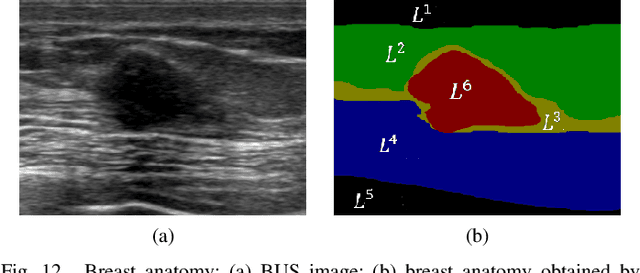

Abstract:Breast cancer is one of the most serious disease affecting women's health. Due to low cost, portable, no radiation, and high efficiency, breast ultrasound (BUS) imaging is the most popular approach for diagnosing early breast cancer. However, ultrasound images are low resolution and poor quality. Thus, developing accurate detection system is a challenging task. In this paper, we propose a fully automatic segmentation algorithm consisting of two parts: fuzzy fully convolutional network and accurately fine-tuning post-processing based on breast anatomy constraints. In the first part, the image is preprocessed by contrast enhancement, and wavelet features are employed for image augmentation. A fuzzy membership function transforms the augmented BUS images into fuzzy domain. The features from convolutional layers are processed using fuzzy logic as well. The conditional random fields (CRFs) post-process the segmentation result. The location relation among the breast anatomy layers is utilized to improve the performance. The proposed method is applied to the dataset with 325 BUS images, and achieves state-of-art performance compared with that of existing methods with true positive rate 90.33%, false positive rate 9.00%, and intersection over union (IoU) 81.29% on tumor category, and overall intersection over union (mIoU) 80.47% over five categories: fat layer, mammary layer, muscle layer, background, and tumor.

Abstract:Breast cancer investigation is of great significance, and developing tumor detection methodologies is a critical need. However, it is a challenging task for breast ultrasound due to the complicated breast structure and poor quality of the images. In this paper, we propose a novel tumor saliency estimation model guided by enriched breast anatomy knowledge to localize the tumor. Firstly, the breast anatomy layers are generated by a deep neural network. Then we refine the layers by integrating a non-semantic breast anatomy model to solve the problems of incomplete mammary layers. Meanwhile, a new background map generation method weighted by the semantic probability and spatial distance is proposed to improve the performance. The experiment demonstrates that the proposed method with the new background map outperforms four state-of-the-art TSE models with increasing 10% of F_meansure on the BUS public dataset.

Abstract:Tumor saliency estimation aims to localize tumors by modeling the visual stimuli in medical images. However, it is a challenging task for breast ultrasound due to the complicated anatomic structure of the breast and poor image quality; and existing saliency estimation approaches only model generic visual stimuli, e.g., local and global contrast, location, and feature correlation, and achieve poor performance for tumor saliency estimation. In this paper, we propose a novel optimization model to estimate tumor saliency by utilizing breast anatomy. First, we model breast anatomy and decompose breast ultrasound image into layers using Neutro-Connectedness; then utilize the layers to generate the foreground and background maps; and finally propose a novel objective function to estimate the tumor saliency by integrating the foreground map, background map, adaptive center bias, and region-based correlation cues. The extensive experiments demonstrate that the proposed approach obtains more accurate foreground and background maps with the assistance of the breast anatomy; especially, for the images having large or small tumors; meanwhile, the new objective function can handle the images without tumors. The newly proposed method achieves state-of-the-art performance when compared to eight tumor saliency estimation approaches using two breast ultrasound datasets.